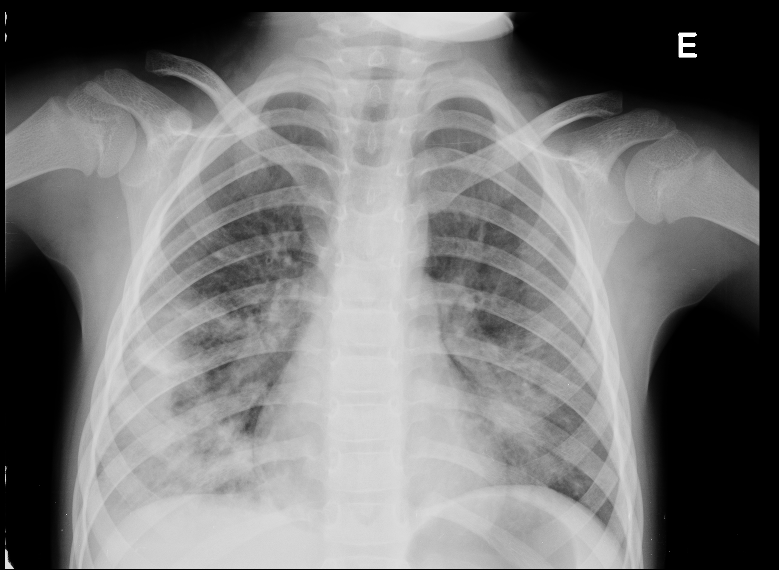

Malformação Pulmonar Congénita Tipo 2

Criança, Malformação Adenomatoide Quística Congénita do Pulmão/diagnóstico, Malformação Adenomatoide Quística Congénita do Pulmão/diagnóstico por imagemDownloads

Images in Pediatrics